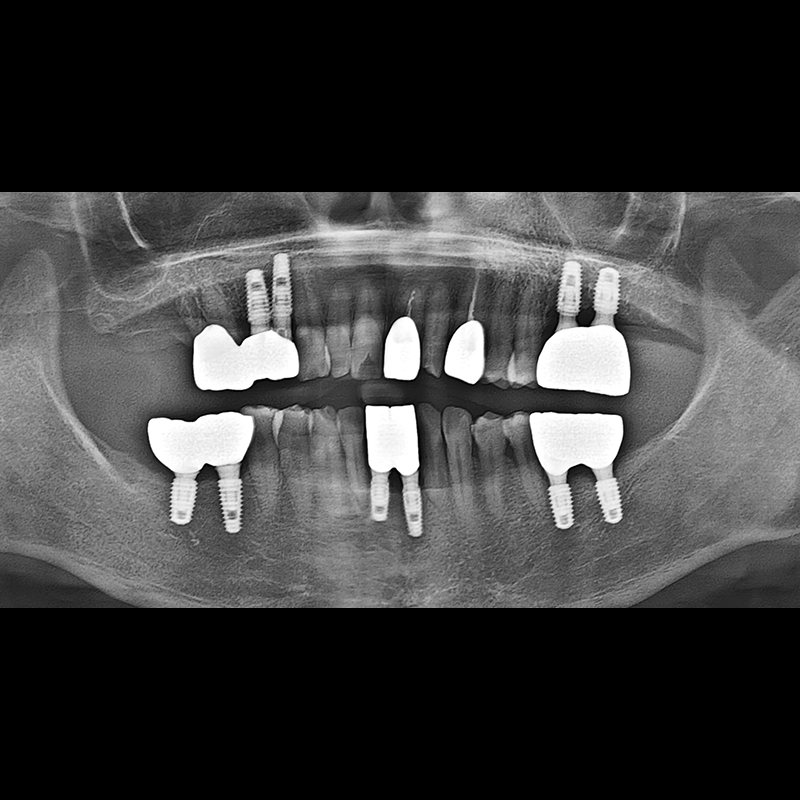

IMPLANT

BEFORE AFTER

Implant before and after 2025.05.30

Implants were placed in the missing tooth and in the tooth position where it was difficult to save.